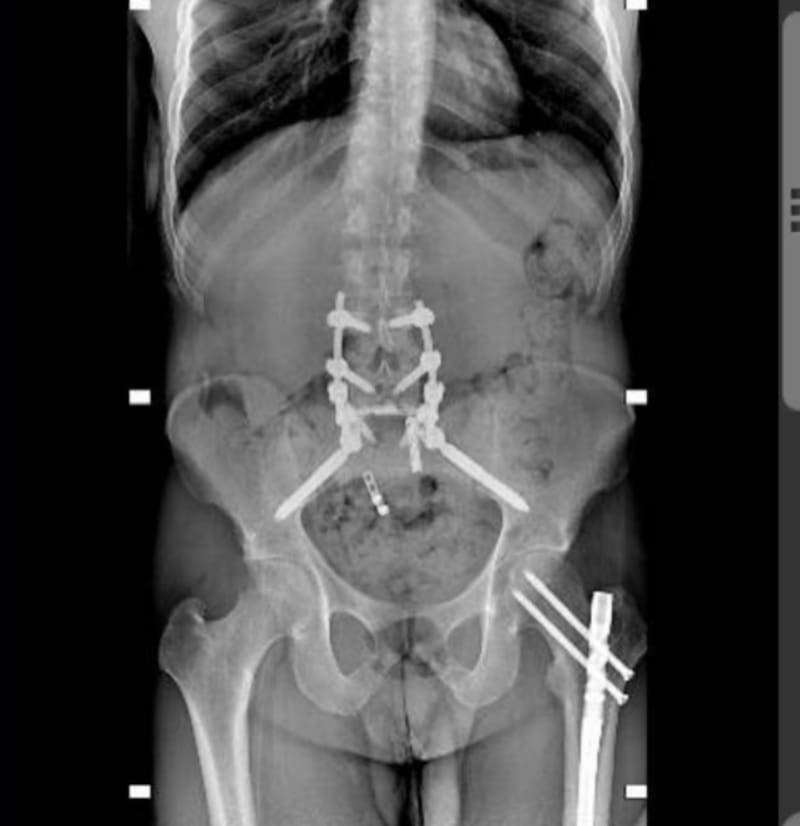

Entonces revivió su paso por el médico donde relata que después de una semana en Rhode Island entraría al quirófano donde al abrirle la espalda solo le encontraron un nervio sacro roto; es decir, un milagro. "Fue entonces cuando las cosas dieron un giro drástico al convertir una cirugía de 16 horas en una cirugía de 6 horas y la noticia de que iba a poder caminar de nuevo", contó.

Fue hasta el 8 de abril cuando por primera vez el hijastro de Lucero, hijo de Michel Kuri (la actual pareja de "La Novia de América") y Ana Paula O'Farril, pudo ponerse de pie. Fue hasta el 16 de abril cuando pudo dar sus primeros pasos con ayuda y esfuerzo.